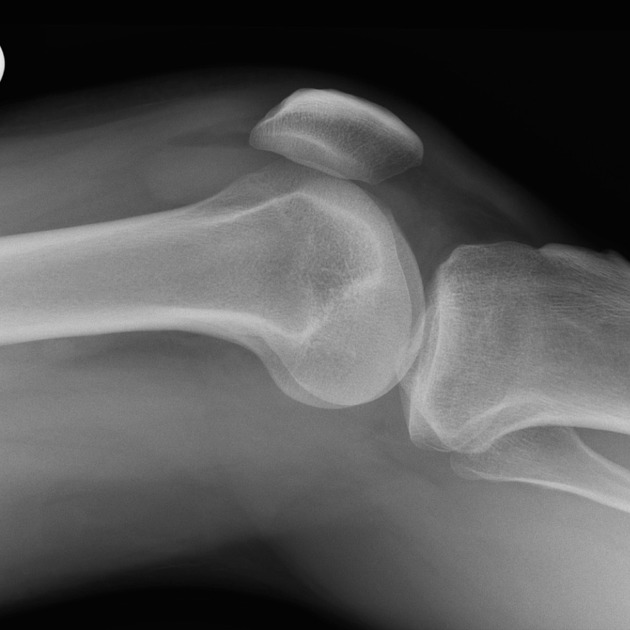

Knee Conditions GET IN TOUCH Knee Arthritis Meniscal Tears ACL Tears Knee Instability The Painful Or Failing Knee Replacement Knee Arthritis Learn MOre Meniscal Tears Learn MOre ACL Tears Learn MOre Knee Instability Learn MOre The Painful Or Failing Knee Replacement Learn MOre KNEE SURGERY OUR SERVICES If joint pain or injury is affecting your daily life, Dr Paterson is here to support your recovery with individualised, evidence-based care. Knee Arthritis Learn MOre Meniscal Tears Learn MOre ACL Tears Learn MOre Knee Instability Learn MOre The Painful Or Failing Knee Replacement Learn MOre OTHER TREATMENT OPTIONS